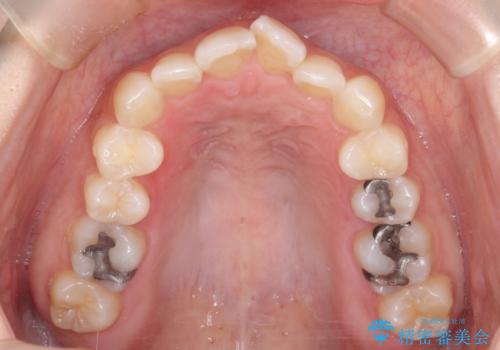

- 口元が出てるのが気になるとのことで来院されました。

上下左右前から4番目の歯を抜歯して前歯を後方に下げて、口元を下げる計画としました。